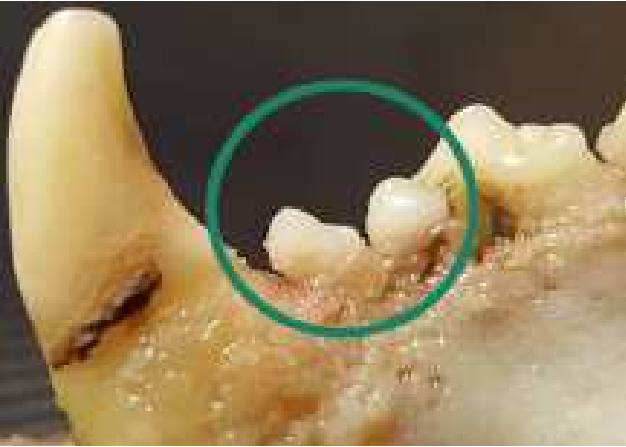

Test Area — Right Upper Jaw

In the test area, where the tooth was removed and MMSCs pre-treated with MBER were implanted, complete regeneration of the tooth was observed after 9 months (initial signs of regeneration were documented at 90 days).

[IMAGE 3 — Figure 1B. Test: Right upper jaw of the test dog. The tooth was removed and multipotent mesenchymal stem cells (MMSCs) pre-treated with MBER were implanted. Regeneration of teeth is visible after 90 days.]

The contrast between the control and test areas provides direct visual and clinical confirmation of the regenerative effect induced by the MBER-reprogrammed stem cells.